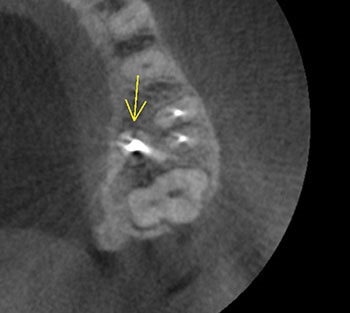

Case 2: A U-shaped lesion

Tooth #30 presented with a diagnosis of previously treated and symptomatic apical periodontitis. The radiographic lesion encompassed both sides of the mesial root, forming a U-shaped lesion. Periodontal probing extended to the apex. The prior endodontic root preparations were relatively large, compared with the root canals on the patient’s other untreated teeth. Because the bone loss associated with a U-shaped lesion encompasses both sides of a root, it might be considered even more indicative of a potential VRF than a J-shaped lesion.

This patient had been examined by an endodontist, who recommended extraction because of a VRF. Although multiple risk factors were identified, no fracture was seen upon access, and this tooth was successfully retained through nonsurgical retreatment.

Fig. 6: Preop CBCT.

Fig. 8: Recall CBCT.